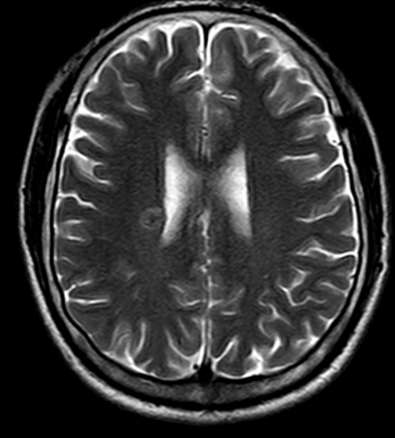

- MRI sọ não:

Hình 4. Trên phim chụp MRI sọ não: Rải rác trong nhu mô trên và dưới lều có các nốt ngấm thuốc, lớn nhất vị trí cạnh não thất bên bên phải đường kính ~11mm – Theo dõi tổn thương thứ phát

Cộng hưởng từ sọ não:

Trước điều trị Sau 3 tháng điều trị

- Sau 6 tháng điều trị: Nhu mô não vùng trên và dưới lều tiểu não: hình dạng và cấu trúc bình thường, tín hiệu đồng nhất, ranh giới chất trắng và chất xám rõ. Không thấy tổn thương khu trú hoặc lan tỏa.